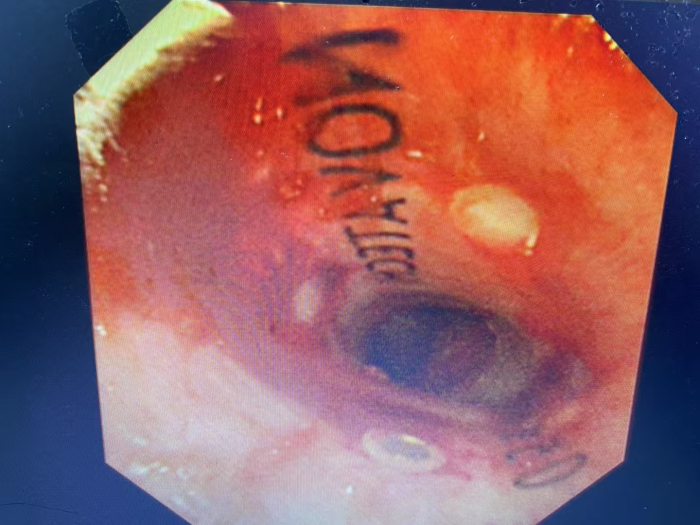

看着黄先生痛苦不已,家属心急如焚,打听到自治区南溪山医院院呼吸与危重症医学科二病区有神奇的呼吸介入手术可缓解呼吸困难,遂于春节期间紧急转至该病区。屈东明博士查看资料后迅速组织完善术前检查,呼吸介入团队联合麻醉科、内镜中心联合制定个性化方案。在全麻下行沙漏型硅酮支架植入术,术中发现患者情况更为严重,因肿瘤侵犯气管扭曲,鞘管无法通过最狭窄部位,同时支架推送器也无法通过鞘管。呼吸介入团队经过商量后迅速调整手术方案,终于成功植入气道支架,患者从“命悬一线”到自由呼吸!

屈东明博士介绍:硬质气管镜下置入支架,通俗来讲,就是在不开刀的情况把狭窄的气管扩张到趋于正常气道的大小。气管支架置入术是一项高风险、高难度的医疗技术,尤其是恶性肿瘤压迫气道狭窄的患者。动作轻了、慢了,支架无法通过狭窄或者卡在了狭窄部位,有可能造成患者窒息,手术失败。动作用力过猛,又很有可能造成气道损伤加重,术后并发症增多。